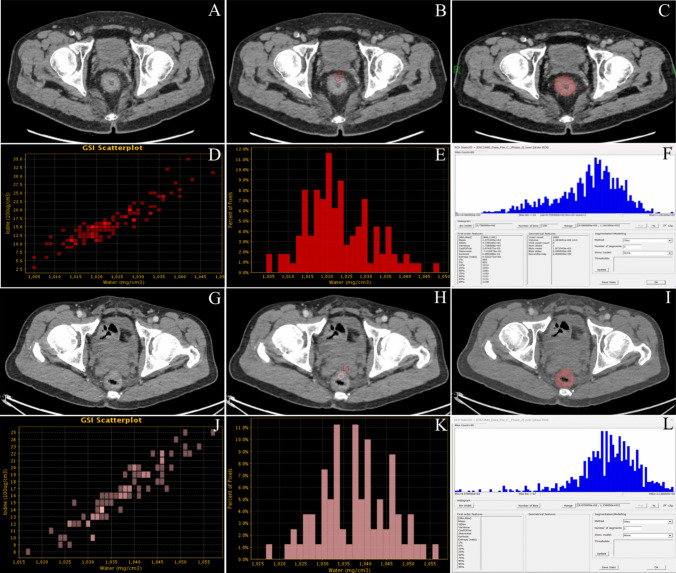

Purpose: The purpose is to evaluate the predictive value of dual-energy CT (DECT) combined with histogram parameters and a clinical prediction model for perineural invasion (PNI) in colorectal cancer (CRC).

Methods: We retrospectively analyzed clinical and imaging data from 173 CRC patients who underwent preoperative DECT-enhanced scanning at two centers. Data from Qinghai University Affiliated Hospital (n = 120) were randomly divided into training and validation sets, while data from Lanzhou University Second Hospital (n = 53) served as the external validation set. Regions of interest (ROIs) were delineated to extract spectral and histogram parameters, and multivariate logistic regression identified optimal predictors. Six machine learning models-support vector machine (SVM), decision tree (DT), random forest (RF), logistic regression (LR), k-nearest neighbors (KNN), and extreme gradient boosting (XGBoost)-were constructed. Model performance and clinical utility were assessed using receiver operating characteristic (ROC) curves, calibration curves, and decision curve analysis (DCA).

Results: Four independent predictive factors were identified through multivariate analysis: entropy, CT40KeV, CEA, and skewness. Among the six classifier models, RF model demonstrated the best performance in the training set (AUC = 0.918, 95% CI: 0.862-0.969). In the validation set, RF outperformed other models (AUC = 0.885, 95% CI: 0.772-0.972). Notably, in the external validation set, the XGBoost model achieved the highest performance (AUC = 0.823, 95% CI: 0.672-0.945).

Conclusion: Dual-energy CT-based combined with histogram parameters and clinical prediction modeling can be effectively used for preoperative noninvasive assessment of perineural invasion in colorectal cancer.